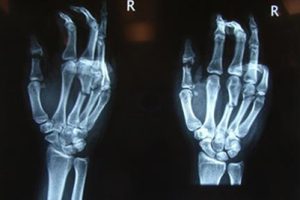

Çok sayıda kırık kemik ve kesik tendona sahip ezilmiş el. Kırıkların düzeltilmesi ve tendonların, elin uzun süre hareketsiz kalmasına gerek kalmadan ameliyattan hemen sonra rehabilitasyona izin veren teknikler kullanılarak onarılması gerekir.